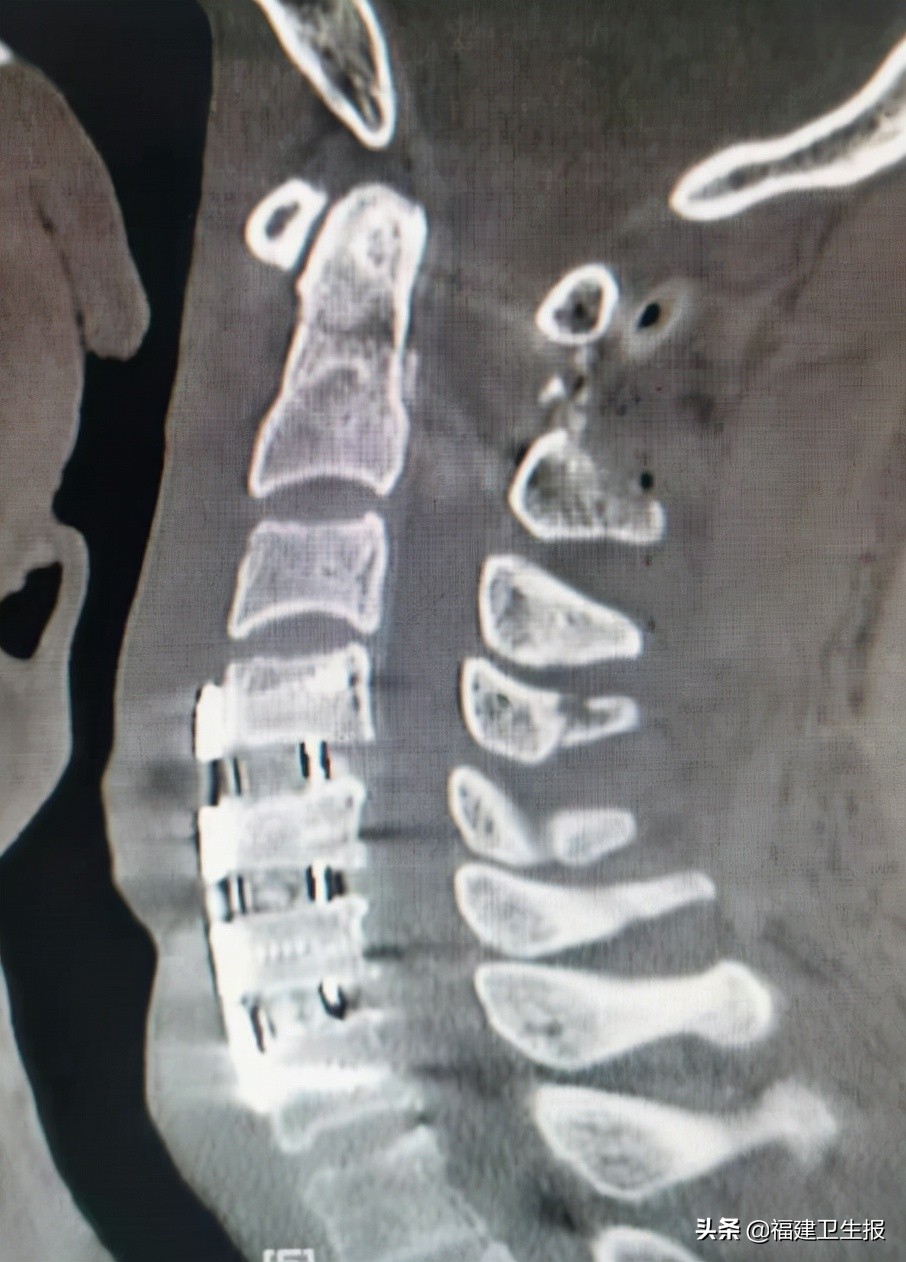

术后患者很快恢复清醒,四肢开始活动。术后第一天患者双上肢可自行举起,双手握力开始恢复。术后第5天患者各引流管均拔除,佩戴颈托自行下地步行良好,双上肢肌力恢复正常,下肢肌力正常,各项生活可自理,复查颈椎X线片及颈椎CT见枢椎齿状突骨折及寰椎复位良好,内固定精准在位。

▲术后复查颈椎X光

▲CT